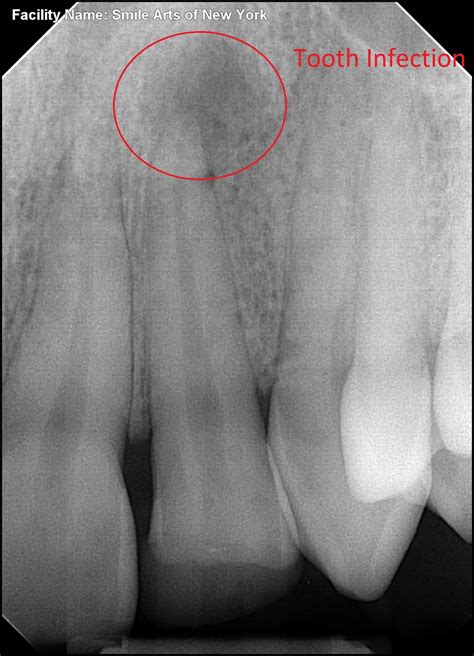

1. Diagnosis and Anesthesia: Your dentist will take X-rays to visualize the internal structure of the tooth. A local anesthetic is administered to ensure the area is completely numb.

A root canal becomes necessary when the soft tissue inside the tooth, called the pulp, becomes infected or inflamed. This often happens due to deep decay, repeated dental procedures, faulty crowns, or trauma to the face. Because front teeth have only one root and one canal, the procedure is often faster and less complex than it is for molars.